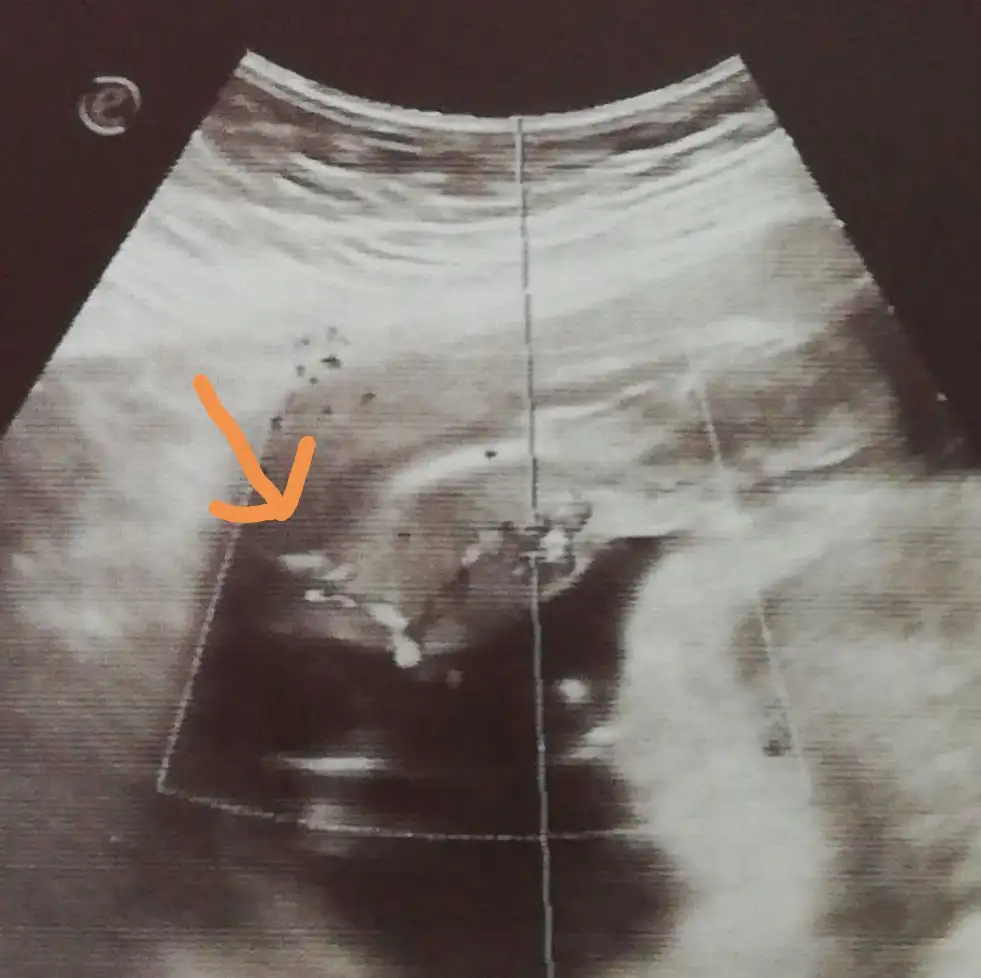

Hiç net değil ki bu görüntü ,ben bebeğin nerde olduğunu bile anlayamadım,devletin ultrasyonu mu bu ?

devletin ultrasonu canım. bebek yatıyo aslında ama, göremediysen canın sağolsun canım önemli değilHiç net değil ki bu görüntü ,ben bebeğin nerde olduğunu bile anlayamadım,devletin ultrasyonu mu bu ?

renkliden bişi anlamadım ama nubdan bana kız gibi geldi. kafanızı karıştırmayayım bu işten çok anlamıyorum. Anlasam kendi fotoğrafımı direk bilir, kimseye sormazdımYa kızlar bugün arkadaşlarla toplandık ultrason görüntülerime baktılar.

Bir çoğu yok emin olma o kadar yoksa %100 derdi değişebilir o dediler..yani doktor bir şey görmese erkek der mi ? Ben bile sanki fark ediyorum renklide..

Ama ona da Göbek bağı olabilir diyolar..

Gercekten erkek olduğu belli olmuyor mu sizce de ?